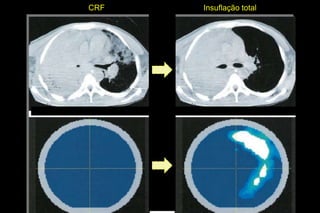

CRF   Insuflação total

Análise de multipla regressão para variações locais de impendância

durante insuflação lenta (standard electrode positioning) quando

projetado sobre mudanças sincronizadas nas imagens de TC de tórax.

Análise de multiplaregressão para variações locais de impendância durante insuflação lenta (standard electrode positioning) quando projetado sobre mudanças sincronizadas nas imagens de TC de tórax.